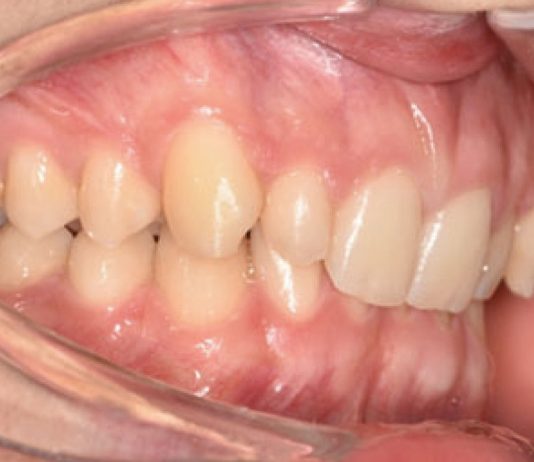

Malocclusione di classe II con morso profondo e lieve affollamento superiore anteriore trattata con...

La malocclusione di classe II può essere distinta in scheletrica e dentale. La malocclusione scheletrica di classe II si riferisce più spesso a una...